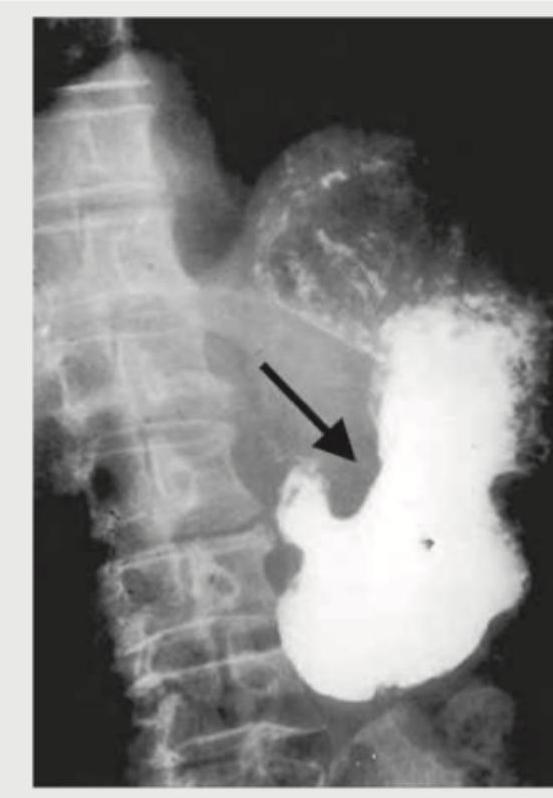

What is the diagnosis based on the barium meal study shown below?

Explanation: ***Peptic ulcer disease*** - The barium meal study shows a distinct **niche** (pocket of barium) within the gastric wall, indicated by the arrow, consistent with an **ulcer crater** - Additionally, there is evidence of **gastric wall edema** and possibly **converging folds** around the ulcer, which are typical radiographic findings in peptic ulcer disease - The smooth, round contour of the niche with radiating folds is characteristic of a **benign gastric ulcer** *Gastric carcinoma* - Gastric carcinoma typically appears as an **irregular, nodular filling defect** with shouldering and abrupt transitions - Malignant ulcers have **irregular margins**, do not show converging folds, and lack the smooth contour seen in this image - The benign features of the ulcer crater here make carcinoma unlikely *Esophageal varices* - Esophageal varices would appear as **serpiginous filling defects** or a "rosary bead" appearance within the esophagus - They are not typically seen in the stomach and do not create a niche or ulcer crater - This image shows findings in the stomach or duodenum, not the esophagus *Hiatal hernia* - Hiatal hernia presents as **herniation of the gastric fundus** through the diaphragmatic hiatus into the thoracic cavity - It appears as a **retrocardiac gas bubble** or mass above the diaphragm on barium studies - No evidence of herniation or diaphragmatic abnormality is seen in this image; the findings are localized to an ulcer crater